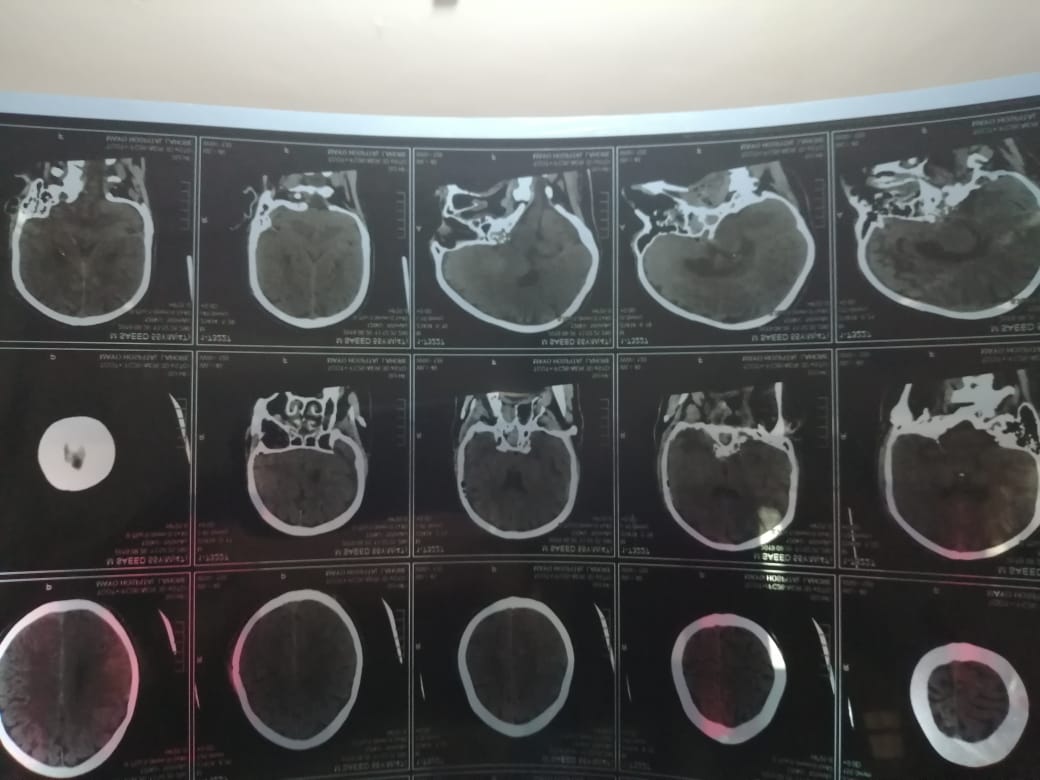

I am asking a question about my father in law he had an accident(second accident of the same type) last week he had a severe head injury. The doctors in Mayo Hospital Neurosurgery department have diagnosed the injury to be diffused axonal injury. The problem is that he is very weak now.(HB is 6) He is not able to take oral intake of medicine and meals and he is not able to relax mucus in his throat, and whatever he eats goes to his airway and causes irritation. This issue has been developed due to some motor nerve damage or what I do not for a doctor who would check in detail and give us solutions for problems which are interlinked i do not know who to go to Neurologist, Neurosurgeon or ENT.

Attach Photo here: